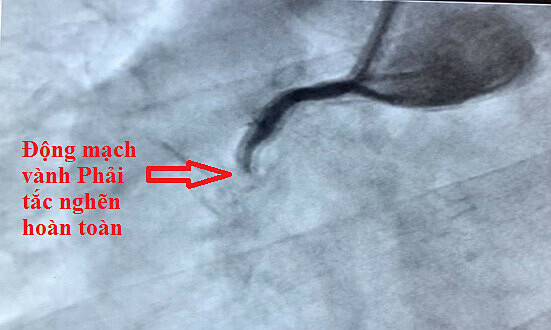

Bác sĩ xác nhận rằng anh ta bị đột quỵ do xuất huyết. Sau khi được cấp cứu, bệnh nhân đã qua cơn nguy kịch, nhưng di chứng để lại là chuột rút, không đi lại được.